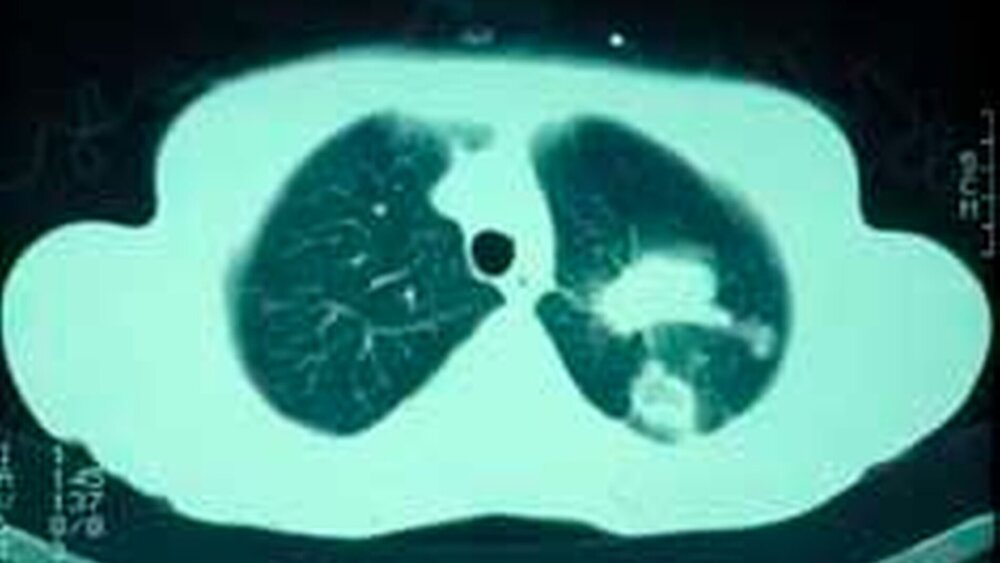

Die histologische Untersuchung der Gewebeprobe zeigte maligne, anaplastische, zytoplasmaarme Zellen mit ausgeprägter Kernpolymorphie und Hyperchromatismus (Abb. 5). Das im Rahmen der anschließenden Primärtumorsuche durchgeführte Computertomogramm des Thorax führte schließlich zur Entdeckung eines zentralen, kleinzelligen Bronchialkarzinoms im Bereich der linken Lunge (Abb. 6). Wenige Monate später verstarb die Patientin an ihrem Tumorleiden.